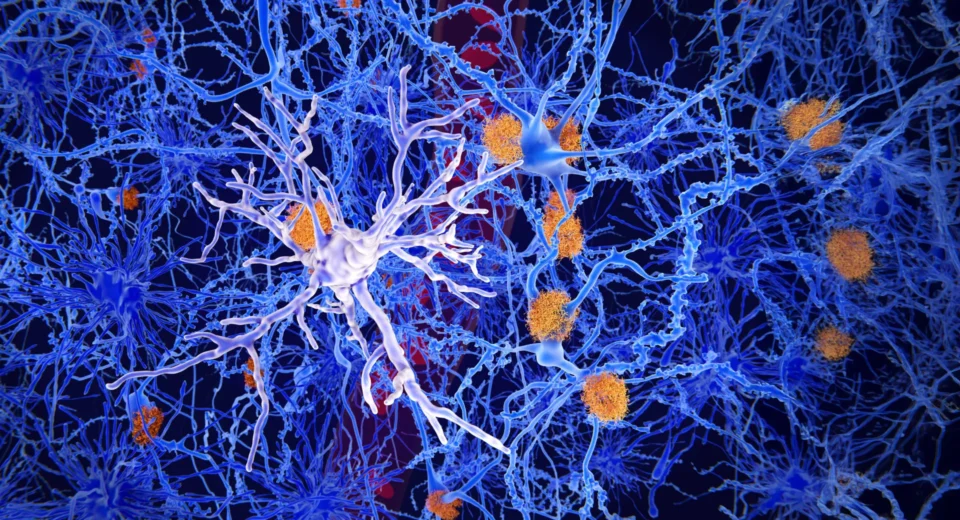

Impactos repetidos na cabeça podem danificar silenciosamente o sistema de limpeza do cérebro

Um novo estudo que examina boxeadores profissionais e lutadores de artes marciais mistas com comprometimento cognitivo relata que o sistema de eliminação de resíduos do cérebro parece enfraquecer após repetidos golpes na cabeça. Esses achados estão programados para serem apresentados na próxima semana na reunião anual da Sociedade Radiológica da América do Norte (RSNA). Lesões […]